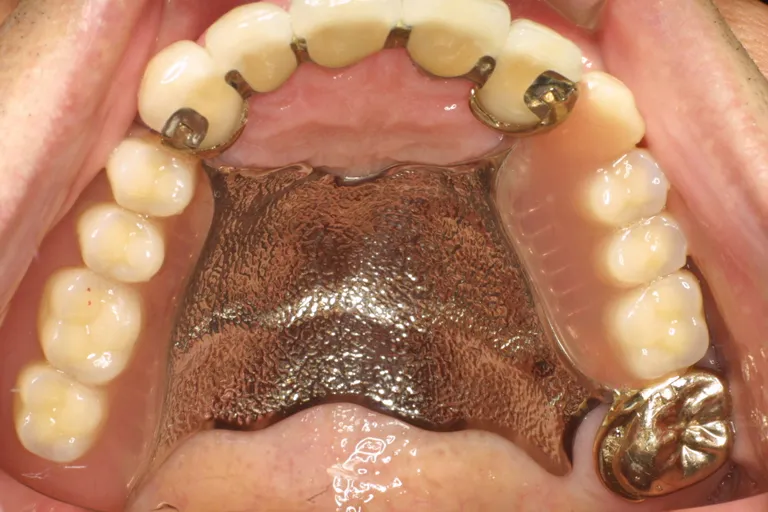

■口の状態・上顎

■口の状態■

上顎